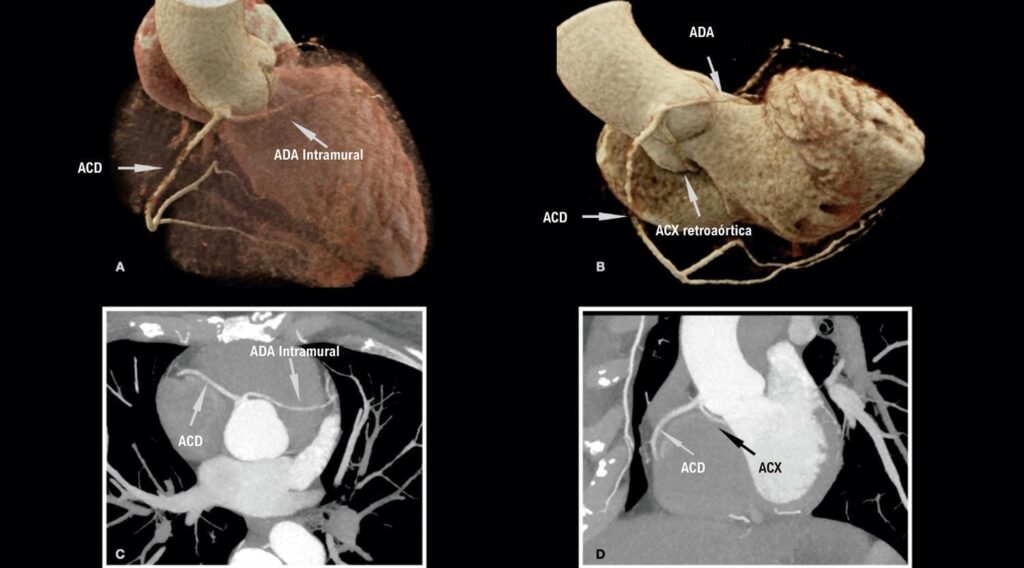

Rara Apresentação de Anomalia Congênita Anatômica de Artérias Coronárias em Exame de Angiotomografia

A origem anômala das artérias coronárias representa um grupo heterogêneo de alterações na origem e trajeto destes vasos, variando desde as mais comuns, assintomáticas e de baixo risco, às mais raras e de maior risco que eventualmente podem ser sintomáticas ou ter como primeira manifestação morte súbita., Sua prevalência corresponde a 1,3% dos pacientes submetidos à angiografia coronária, mas esse número pode ser maior dependendo do método diagnóstico e da população selecionada, representando a segunda maior causa de morte súbita em atletas jovens, atrás apenas da cardiomiopatia hipertrófica.,

Dentro desse grupo, as anomalias de coronária que apresentam óstio único estão presentes em uma menor parte da população, cerca de 0,004% a 0,098%. Na maioria das vezes apresentam-se de forma assintomática, mas podem se manifestar com dor torácica, dispneia, palpitação, infarto de miocárdio e morte súbita., A apresentação desta anomalia tem pior prognóstico na presença de trajeto do vaso interarterial (entre a aorta e tronco pulmonar), ângulo de origem agudo e na presença de placa aterosclerótica, alteração essa que tem maior incidência em vasos anômalos, visto o maior estresse na parede arterial., Além de se apresentarem de forma isolada, podem ainda estar associadas a outras alterações como fístulas cardíacas ou à valva aórtica bicúspide.